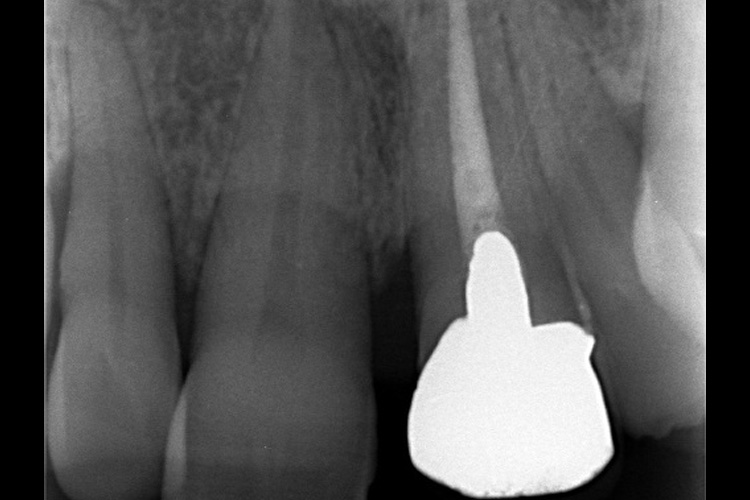

“実際の実施例1”

この患者様は、口腔内全体において重度の歯周病が生じており、歯磨き指導、クリーニング、Flap手術等を行ったが、歯周ポケットが深すぎるため、ブルーラジカル適用症例と診断し、施術を行いました。

(実施前)

施術前のレントゲンと口腔内写真です。施術前にプラークの除去を行ってから、施術します。